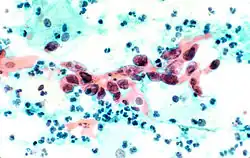

Squamous Cell Carcinoma, bronchial washing.

The stain should result in cells that are fairly transparent so even thicker specimens with overlapping cells can be interpreted.[2] Cell nuclei should be crisp, blue to black in color[12][13] and the chromatin patterns of the nucleus should be well defined. Cell cytoplasm stains blue-green and keratin stains orange in color.[13][5]

Eosin Y stains the superficial epithelial squamous cells, nucleoli, cilia, and red blood cells.[2] Light Green SF yellowish confers a blue staining for the cytoplasm of active cells such as columnar cells, parabasal squamous cells, and intermediate squamous cells.[14] Superficial cells are orange to pink, and intermediate and parabasal cells are turquoise green to blue.[12]